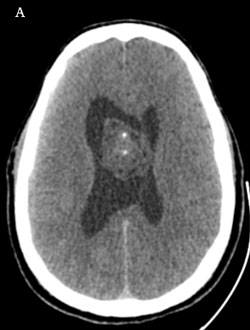

Une tumeur ventriculaire simulatrice

Dr Arnault Tauziède-Espariat AP-HP Lariboisière - Paris , Dr Schahrazed BOUAZZA (Neurochirurgien - CHU de Nice - nice) et Dr Marc Polivka (Pathologiste - Hôpital Lariboisière - Paris cedex 10)

Motif d’hospitalisation : Patient âgé de 46 ans, originaire du Cap-Vert, adressé en urgence pour des céphalées.

Comorbidité : Hypertension artérielle traitée et contrôlée.